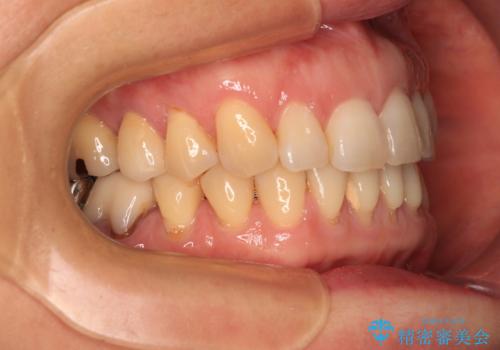

- 飛び出した上顎前歯と正中のズレを気にして来院された患者様です。

上顎正中が右側にずれていたので、むし歯が酷く抜歯が必要な左側臼歯を抜歯して正中を改善することとしました。

左下には新しいセラミックのブリッジが装着されていたため、ブリッジを壊さずに改善できるところまで咬み合わせを改善していくこととしました。